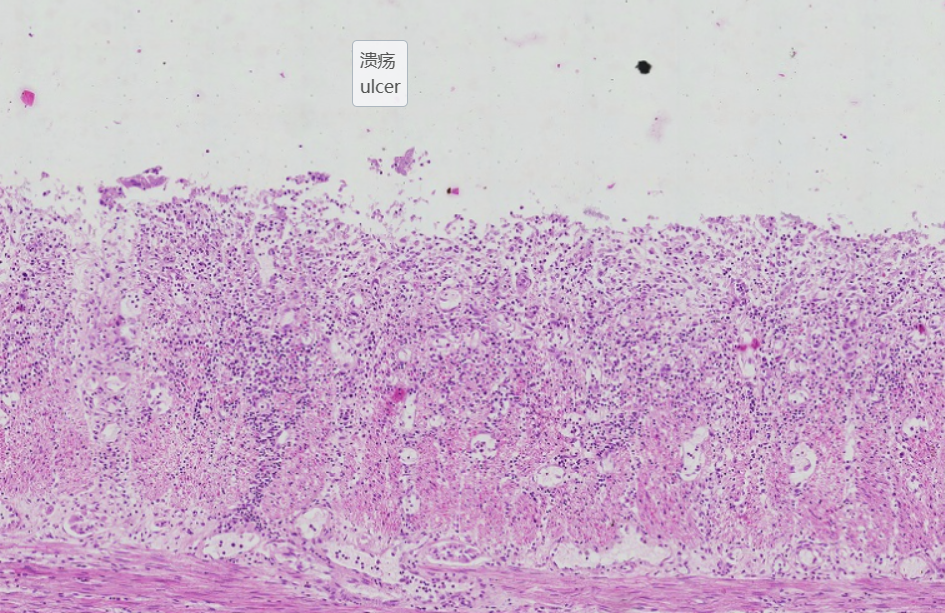

5 胃溃疡